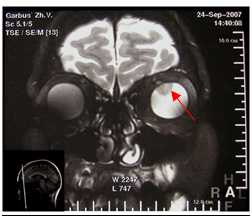

OD: МКОЗ 0,9. Рефракция эмметропическая. Передний отрезок без патологических изменений, оптические среды прозрачные. Диск зрительного нерва бледно-розовый, контуры чёткие. Вокруг диска глубокий желтоватый очаг с чёткими фестончатыми границами и хорошо выраженной поверхностной сосудистой сетью. В зоне папилломакулярного пучка - единичные геморрагии. Над геморрагией фокус гиперпигментации. В макулярной зоне - без патологии. OS: МКОЗ 1,0. Рефракция эмметропическая. Передний и задний отрезок - без патологии. Аутофлюоресценция OD - зона опухоли соответствует гипоаутофлюоресцентному фокусу (зона дегенерации РПЭ). По краям фокуса определяется зона гипераутофлюоресценции, что указывает на увеличение метаболической активности в РПЭ вдоль края опухоли. В зоне активной ХНВ - фокус гипераутофлюоресценции. На флюоресцеиновых ангиограммах OD определяется ранняя пятнистая гиперфлюоресценция с последующим диффузным прокрашиванием в поздние фазы. В проекции ХНВ на ранней стадии определяется зона гиперфлюоресценции с чёткими границами, с усилением просачивания красителя на поздних стадиях. Аутофлюоресценция OS - соответствует норме. На ОКТ OD - в зоне папилломакулярного пучка определяется гиперрефлективный очаг на уровне пигментного эпителия, по краям которого определяются отслойки нейроэпителия. В самой структуре опухоли выявляются гиперрефлективные и гипорефлективные зоны, что соответствует ячеистой структуре кости. ОКТ OS - без патологии. По данным ОКТ-Ангио OD - площадь неоваскулярного комплекса 0,296 мм2. При исследовании светочувствительности макулярной зоны выявлено снижение средней светочувствительности центральной зоны сетчатки OD до 21,0 дБ. Для уточнения диагноза и проведения дифференциальной диагностики были проведены лабораторные тесты и антитела к инфекциям. Антитела были отрицательными. При проведении ультразвукового В-сканирования OD определяется гиперрефлективное образование, дающее орбитальную «тень» в виде «псевдо-ДЗН». Установлен диагноз - OD «остеома хориоидеи», осложнённая хориоидальной неоваскуляризацией правого глаза. С учётом клинической картины пациентке было назначено лечение: проведение интравитреальных инъекций Луцентиса № 3 по стандартной технологии с интервалом в 1 месяц в дозе 0,5 мг (0,05 мл) в условиях стерильной операционной. Критерием для продолжения лечения было сохранение активности ХНВ. При осмотре больной через 3 месяца выявлено повышение МКОЗ OD до 1,0; метаморфопсии не беспокоили. Вокруг диска - глубокий желтоватый очаг с чёткими фестончатыми границами сохраняется. В зоне папилломакулярного пучка - геморрагии не определяются. Интенсивность зоны гиперпигментации усилилась. В макулярной зоне - без изменений. ОКТ OD через 3 месяца - отмечается отсутствие отслоек нейроэпителия. В самой структуре опухоли сохраняются гиперрефлективные и гипорефлективные зоны. По данным ОКТ-Ангио, OD - площадь неоваскулярного комплекса снизилась до 0,166 мм2. Аутофлюоресценция OD - зона опухоли соответствует гипоаутофлюоресцентному фокусу. По краям фокуса определяется зона гипераутофлюоресценции. В зоне ХНВ - фокус гипераутофлюоресценции меньший по площади в сравнении с прежним исследованием. ФАГ OD - в проекции ХНВ на ранней стадии зона слабой гиперфлюоресценции меньшая по площади в сравнении с прежним исследованием. На поздних стадиях усиления просачивания красителя не определяется. В зоне опухоли сохраняется ранняя пятнистая гиперфлюоресценция с последующим диффузным прокрашиванием в поздние фазы. При исследовании светочувствительности макулярной зоны через 3 месяца наблюдения выявлено повышение средней светочувствительности центральной зоны сетчатки OD до 27,0 дБ.

6. КТ\МРТ орбит - бесконтактный метод диагностики, позволяющий в ряде случаев выявить внутриглазное образование, вторичную отслойку сетчатки.